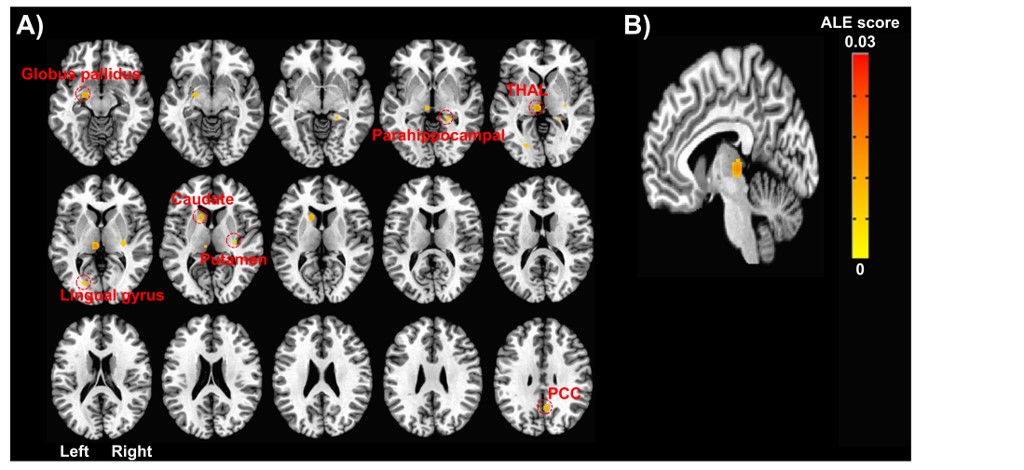

1.jpg경희대학교 한의과대학 김동원 학생(본과 4학년·사진)이 최근 만성 통증의 치료에 따라 체성 감각 변별을 담당하는 뇌 부위의 기능적 활성이 감소하는 반면 포도당 흡수, 혈류 등 대사 활성이 증가한다는 연구결과를 SCI(E) 저널인 ‘Frontiers in Neuroscience’(IF: 4.677)에 게재했다. 또한 이번 연구에서는 감각뿐만 아니라 인지활동의 여러 부분과 관련된 시상(thalamus)의 기능적 활성이 만성 통증의 치료에 따라 유의하게 감소한 것도 함께 확인했다.

그 결과 만성 통증 치료 전후를 비교했을 때, 일차 감각 및 운동 피질과 시상 등의 부분에 대한 기능적 활성이 치료 후에 유의하게 감소하는 경향과 더불어 앞대상회피질(ACC), 뇌섬엽(insula)의 기능적 활성 또한 감소하는 경향이 있다는 것을 확인했다.

또한 이들의 대사 활동도 일차 감각 및 운동 피질과 시상, 그리고 뇌섬엽은 포도당 흡수와 혈류량 증가, 진통 효과와 관련이 있는 뮤(μ) 아편양 수용체 결합 전위가 유의하게 증가하는 것으로 나타났으며, 전대상회피질에서는 반대로 이들 대사 활성이 감소하는 경향으로 나타났다.

특히 이번 연구에서 만성 통증 치료에 가장 일관되게 기능적 활성이 변화하는 것으로 나타난 ‘시상’은 통증 전달 및 조절에 중추적인 역할을 하며, 시상 기능에 장해가 생기면 만성 통증 증상이 나타날 수도 있다는 것을 확인, 이 부위의 기능적 활성 감소 경향은 통증 자극을 더 이상 현저하게 느끼지 않는다는 것을 반영할 가능성이 있으며, 이는 만성 통증에 의해 과민해진 뇌의 통증 처리 활동이 치료에 의해 개선되었기 때문으로 분석했다.